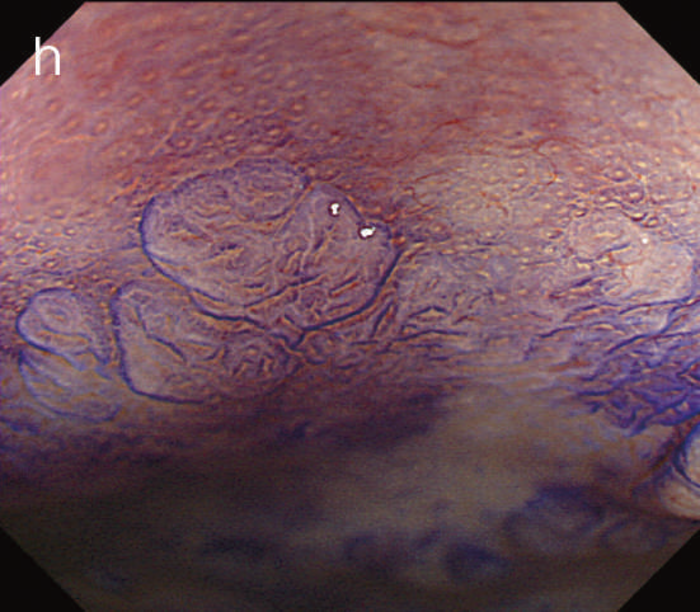

- 術式の選択

UCに対する代表的な術式を図13に示した。UC関連大腸癌の場合,散発性大腸癌に比べて,腫瘍組織と非腫瘍組織の区別が難しい症例も多く,病変の周囲にdysplasiaを合併している症例も多いため,特に下部直腸に病変を有している症例では,術式の選択は慎重に行うべきである。

(1)大腸全摘,回腸囊肛門吻合術(Ileoanal anastomosis:IAA)

直腸粘膜をすべて切除し,回腸囊と肛門を手縫い吻合する。UCに対しても根治性が高い術式である。図14のように,肛門管粘膜の切除開始ラインは歯状線の肛門側で,肛門陰窩をすべて切除する。切除開始ラインが歯状線よりも口側になり,一部肛門管粘膜(移行帯上皮)を温存させた結果,この残存した粘膜からの発癌を強く示唆する症例報告も存在する2)。また,IAAを行ったにもかかわらず,術後に発癌したという症例報告も存在するが,多くは術後3年以内に発症している症例が多く,術前の直腸癌の局所再発が原因ではないかとの意見が一般的である3)。下部直腸から肛門管にかけて早期癌を合併するような症例では,術後の病理検査で,DM0,RM0であっても図15のように局所再発を生じる可能性もあるので,定期的な画像診断とともに,直腸診を行い,局所再発がないことを確認すべきである4)。

CQ 16で述べたように,UC関連大腸腫瘍を合併した症例に対してはIAAが推奨されるが,技術的にIAAが実施可能な体型かという問題も考慮しなければならない。図16のように回腸間膜を開窓してpouch topの位置確認を行うが,恥骨結節の下縁よりも少なくとも2 cm程度肛門側まで進展しない場合は,肛門吻合は難しい。術中判断で回腸囊が肛門まで到達することが困難な症例では回腸囊肛門管吻合術(ileoanal canal anastomosis:IACA)+術後のATZ(anal transitional zone)の内視鏡的サーベイランスという選択肢も考慮する必要がある。ただ,下部直腸に腫瘍が存在する場合はこの選択はできない症例もあり,大腸全摘,永久回腸人工肛門造設術が必要になることもあるので,術前に十分にインフォームドコンセントを得ておく必要がある。(2)大腸全摘,回腸囊肛門管吻合術(ileoanal canal anastomosis:IACA)

回腸囊と肛門管を器械吻合して肛門管粘膜を温存する術式である。IAAと比べて括約筋機能は良好であるという報告が多い反面,残存肛門管粘膜からの発癌症例もみられ,術後は残存肛門管粘膜に対する内視鏡的サーベイランスが必要である。図17にIACA後に残存肛門管から発癌した症例の切除標本を示す5)。できるだけ残存肛門管粘膜を少なくするために,後壁は歯状線近傍で吻合を行う,double stapling technique(DST)も報告されているが,この術式も体型による影響を受け,肥満体型の男性には低位での吻合は困難である6)。

図13 潰瘍性大腸炎に対する主な術式

(3)大腸全摘,永久回腸人工肛門造設術

CQ 17でも示したように肛門温存が不可能な下部直腸の進行癌症例や最近増加が著しい,ADLの低下している高齢者に対して選択される術式である。術後のQOLを考えると,高齢者に対しては括約筋温存手術よりも良好である症例も多い。

(4)大腸亜全摘,回腸直腸吻合術(ileorectal anastomosis:IRA)

この術式は最も罹患歴の長い直腸を温存させる術式であるため,残存直腸の炎症のコントロールの問題だけでなく,直腸からの発癌症例の報告例も増加し,現在では直腸の炎症が軽微な高齢者など,条件を満たす症例以外には行われていない。残存直腸の炎症のコントロールや,残存直腸に対するサーベイランスが必要である。図18にIRA後に残存直腸から発癌した症例の切除標本を示した。